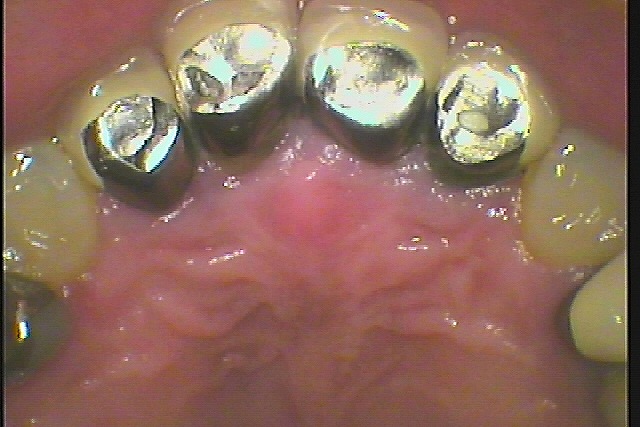

このようなクラウンが入っています